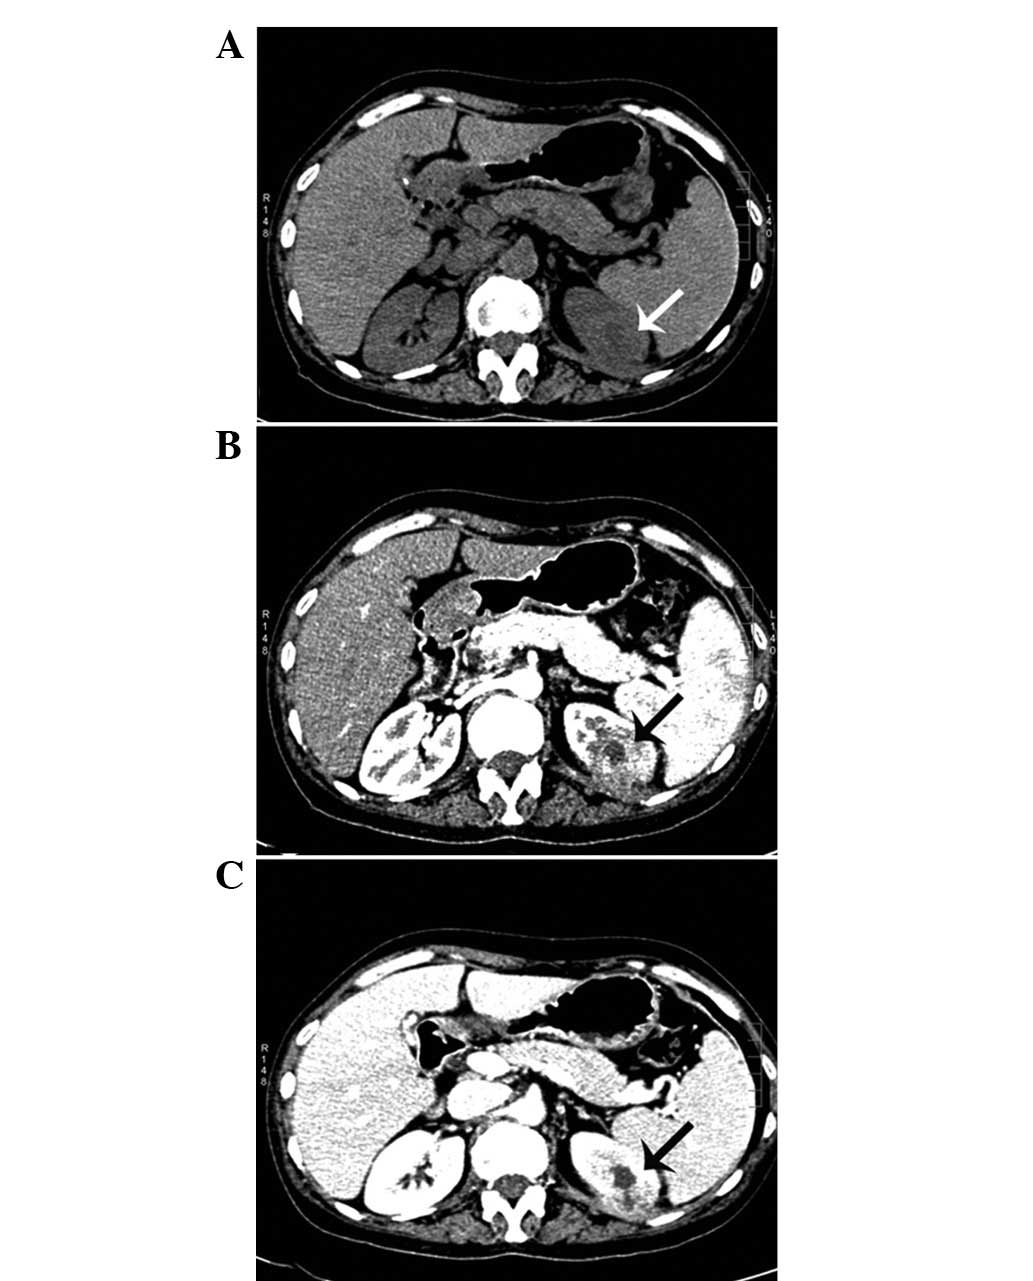

A 48-year-old female visited the First Hospital, Jilin University (Jilin, China) for routine check-up for hepatitis B on July 19, 2012 and presented with no symptoms. The patient had a history of trauma to the left hypochondrium 13 years previously and a history of hepatitis B for 20 years. The latter developed into hepatic cirrhosis, hypersplenism and coagulation disorders. The physical and basic paraclinical examinations were normal. Blood tests revealed a leukocyte count of 2850/mm3, a hemoglobin count of 5.6 g/dl, a platelet count of 6700/mm3, a urine leukocyte count of 20.1/HPF and a urine erythrocyte count of 2.5/HPF. The thrombin time was 19.4 sec and the prothrombin time was 14.0 sec. The international normalized ratio was 1.21, the prothrombin ratio was 1.22 and the prothrombin activity was 69%. Clinical laboratory measurments revealed the following levels: Serum fibrinogen, 0.55 g/l; hepatitis B virus surface antigen (HBsAg), 197.260 IU/Ml; hepatitis B virus e antigen, 0.299S/CO; hepatitis B virus e antibody, 0.110S/CO; and hepatitis B virus core antibody, 18.210S/CO. An abdominal ultrasonography revealed a 1.4×1.4-cm-sized mass with an obscure boundary in the upper pole of the kidney, which protruded through the surface. The computed tomography (CT) scan revealed a 1.6×2.9×2.0-cm lesion in the upper pole of the kidney. The CT was slightly enhanced with contrast (Fig. 1). The magnetic resonance imaging revealed a heterogeneous mass measuring 2.6 cm, showing low intensity on the T1-weighted images and high intensity on the T2-weighted images, which was accompanied with hypointensity that surrounded the center of the lesion (Fig. 2). A radical nephrectomy was performed. The histopathological examination resulted in the lesion being diagnosed as an IMT, in which spindle cells were admixed with variable amounts of extracellular collagen, lymphocytes and plasma cells (Fig. 3). Immunostaining was positive for vimentin and focally positive for smooth muscle actin, desmin and Ki-67 (Fig. 4). There was no evidence of recurrence during a follow-up period of six months.

Figure 1

(A) Computed tomography (CT) scan showing a 1.6×2.9×2.0-cm lesion in the upper pole of the kidney (arrow). (B and C) Contrast-enhanced CT scans showing marginal enhancement (arrow).